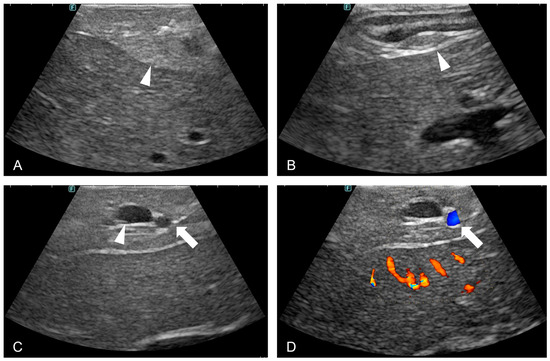

3.2. Laparoscopic Ultrasound

3.3. Pancreatic Biopsy